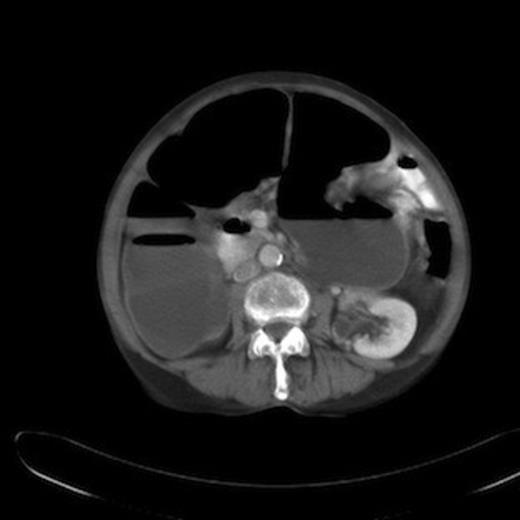

In a majority of cases, the diagnosis is confirmed at exploratory laparotomy. In this case, a CT scan done five months before the acute presentation revealed colonic dilatation and local relapse at the splenic flexure along with liver metastasis and peritoneal disease (Figure 2). A diagnosis of colonic mucocele was not made and the air fluid level in the closed loop was thought to be due to competent ileocaecal valve. On hindsight, the absence of intestinal obstruction in spite of impressive colonic dilatation in the CT scan should have raised the suspicion of an evolving colonic mucocele. This reinforces the need for a high index of suspicion so that the diagnosis can be made pre-operatively and the patient managed conservatively.

CT abdomen showing dilatation of ascending and transverse colon upto splenic flexure with air fluid levels.